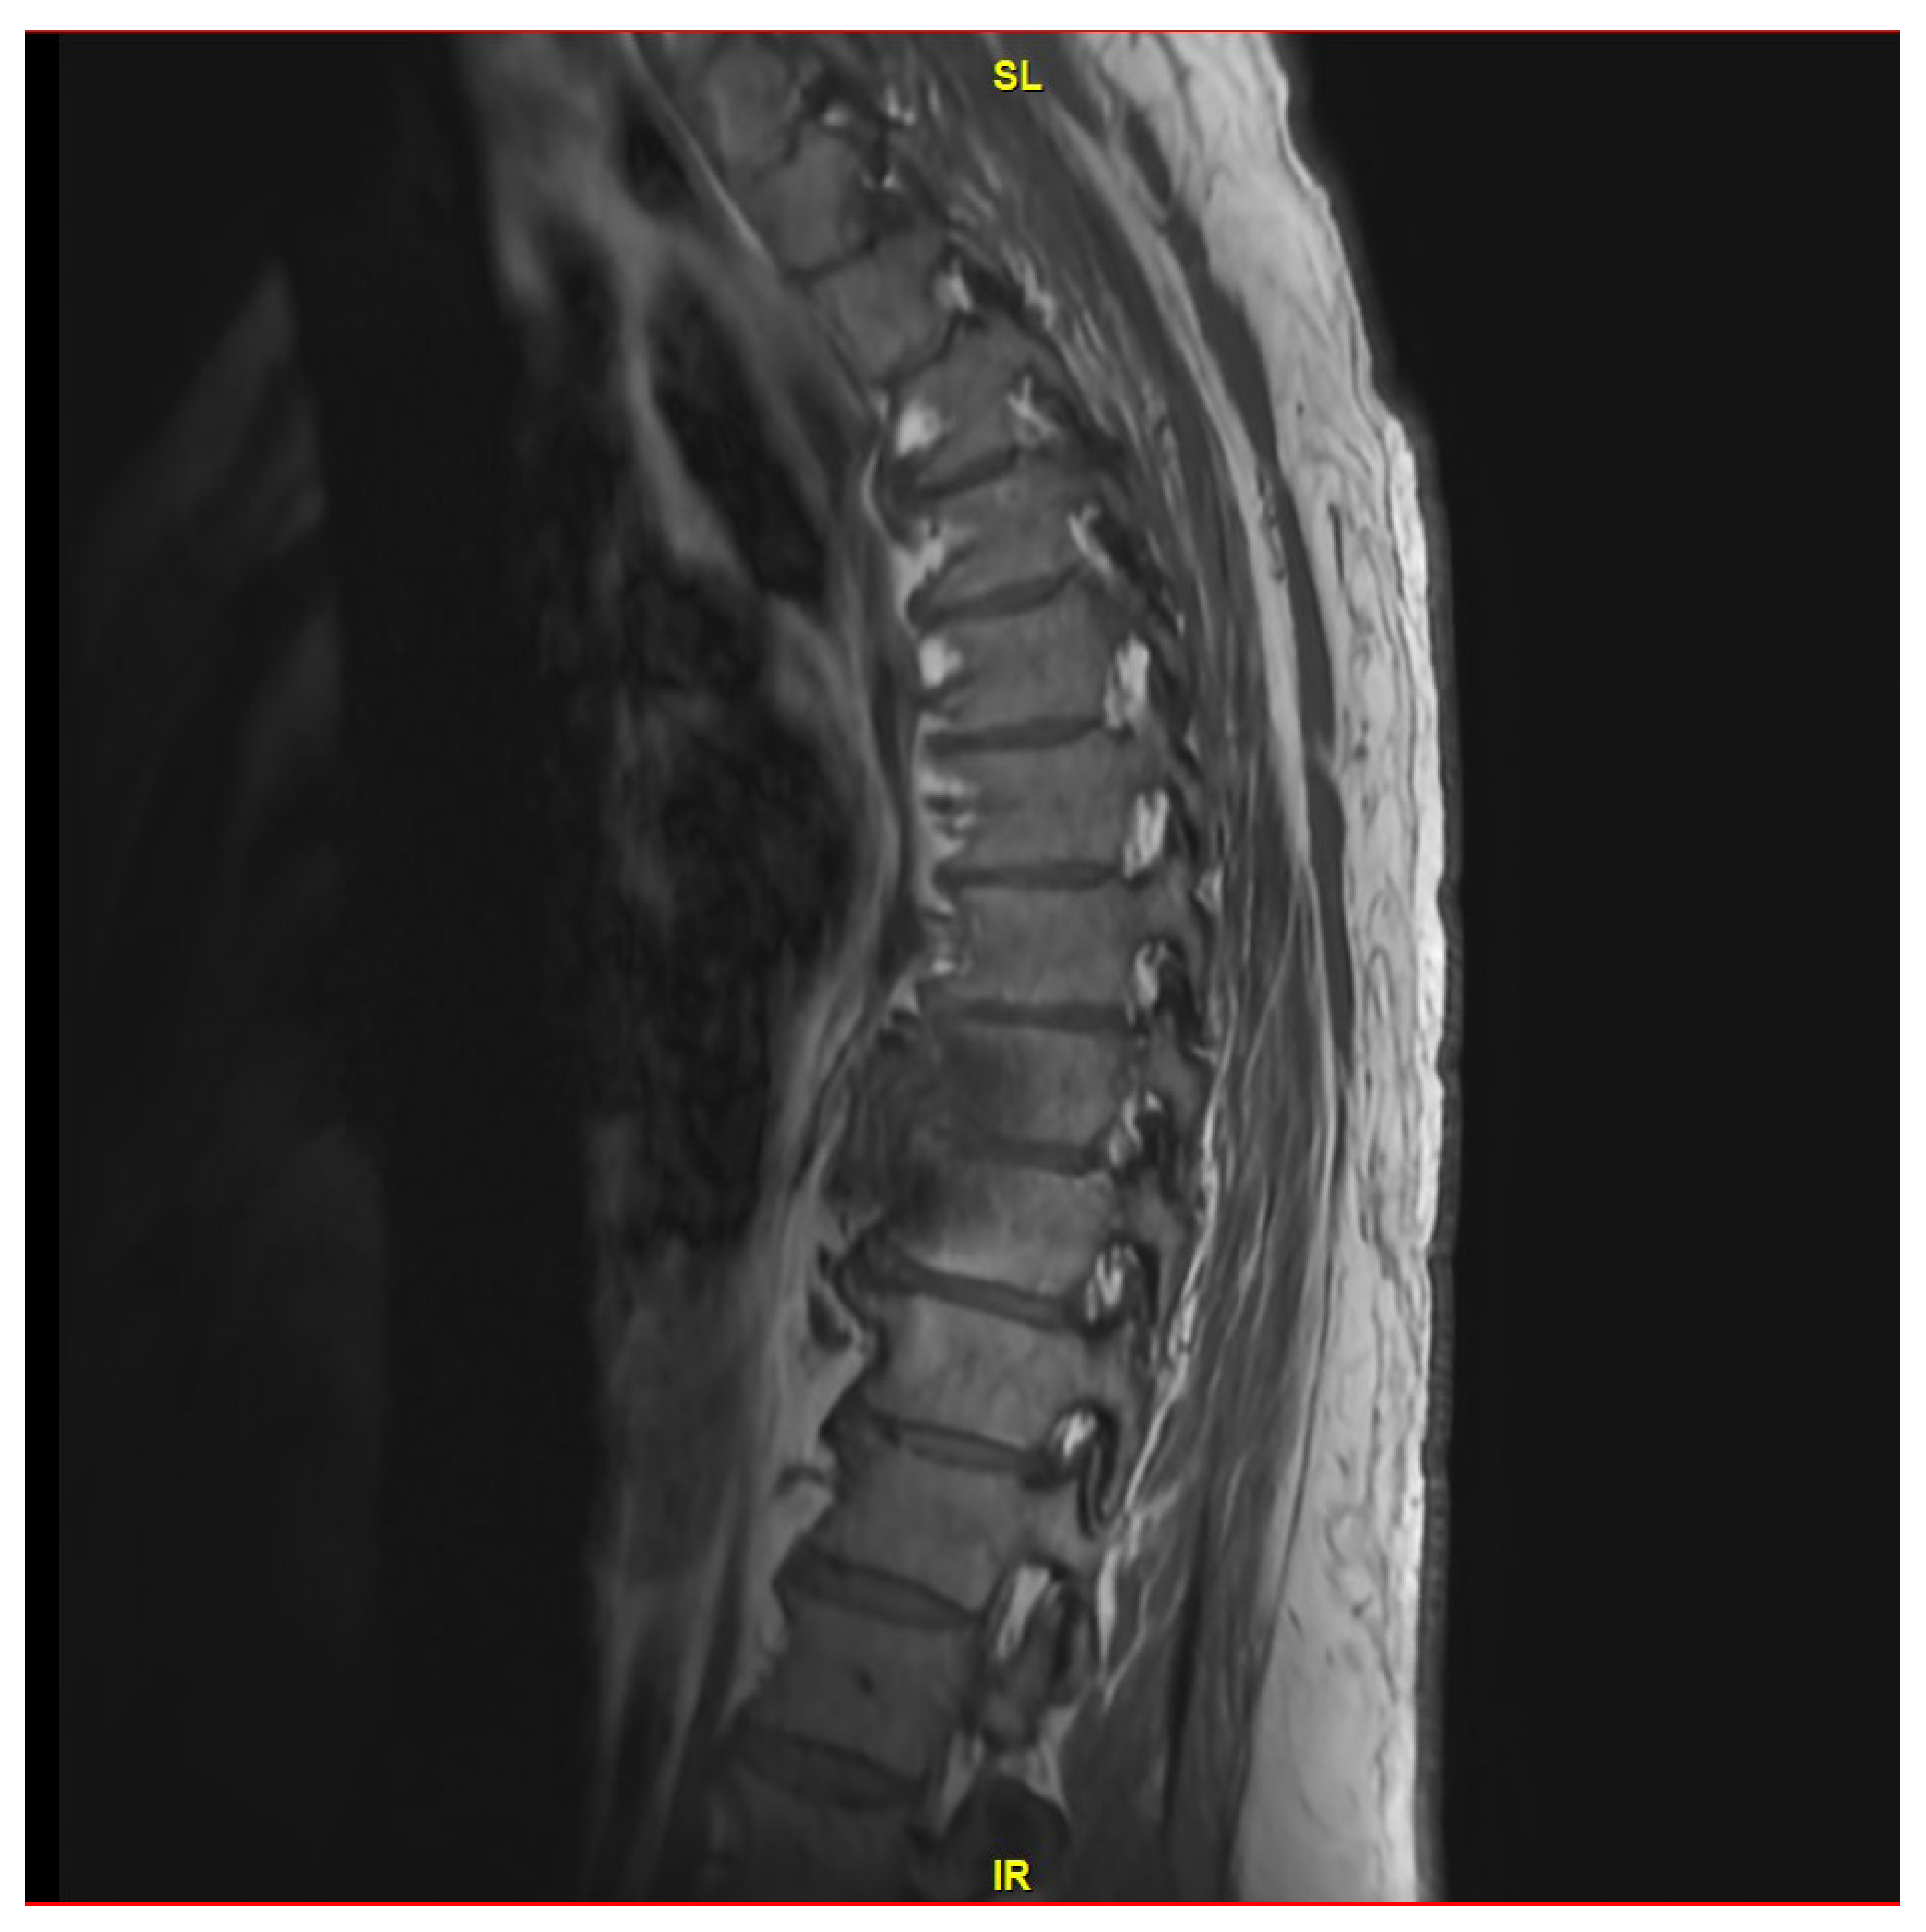

He was evaluated by Neurosurgery on 27 September 2023, and they felt the final recommendations for surgical removal of his hardware were not indicated at this time. He followed up with infectious diseases again on 11 December 2023 after undergoing a repeat MRI of the thoracic spine on December 8th, demonstrating complete resolution of the T8-T9 disc space infection (Figure 3). At that time, the patient reported no back pain and was not requiring pain medication. Considering his L5-S1 spinal fusion hardware, he continued his suppressive oral cefuroxime.

Figure 3. MRI thoracic spine with and without IV contrast showing a completely resolved T8-T9 disc space infection.